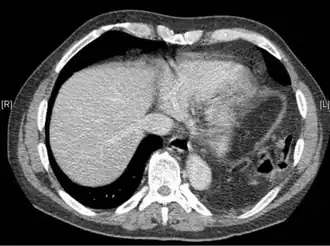

La TC tiene una mayor precisión diagnóstica que los rayos X,[7] pero no existen hallazgos específicos en una TC para establecer un diagnóstico.[9] El borde libre de un diafragma roto puede curvarse y quedar perpendicular a la pared torácica, signo conocido como diafragma colgante. Un órgano herniado puede contraerse en el lugar de la rotura, signo conocido como signo del collar. Si el hígado se hernia a través de una rotura en el lado derecho, puede producir dos signos conocidos como signo de la joroba y signo de la banda. El signo de la joroba es una forma del signo del collar en el lado derecho. El signo de la banda es una línea brillante que cruza el hígado. Se cree que es el resultado de la compresión del diafragma roto.[13] Aunque la tomografía computarizada aumenta las posibilidades de diagnosticar la rotura diafragmática antes de la intervención quirúrgica, la tasa de diagnóstico antes de la cirugía sigue siendo de sólo el 31-43,5%.[7] Otro método de diagnóstico es la laparotomía, pero ésta no detecta las roturas diafragmáticas hasta en un 15% de las ocasiones.[4] A menudo, la lesión diafragmática se descubre durante una laparotomía que se realizó debido a otra lesión abdominal.[4] Dado que las laparotomías son más frecuentes en las personas con traumatismos penetrantes que en las que han sufrido una lesión por objeto contundente, la rotura diafragmática se descubre con más frecuencia en estas personas.[14] La toracoscopia es más fiable para detectar roturas diafragmáticas que la laparotomía y es especialmente útil cuando se sospecha una hernia diafragmática crónica.[4]